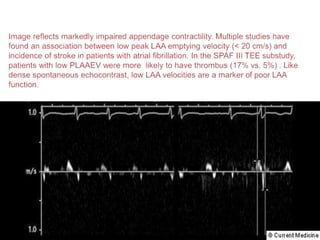

 In LAA/LA clot except type Ia- most of the interventionalist usually

defer PTMC.

 For LA/LAA clot assessment we image LAA in mid esophageal 0

degree and 90-110 degree.

 Second image is obtained by slightly withdrawing TEE probe till

visualization of aorta and image LAA in 0 degree and 90-110 degree

angle with slight counter clock wise probe rotation.

 Severe rheumatic MS specially with associated AF, dilated LA(>4.5

cm),dense spontaneous ECHO contrast and LAA emptying velocity

<25 cm/sec is associated with LAA/LA clot.